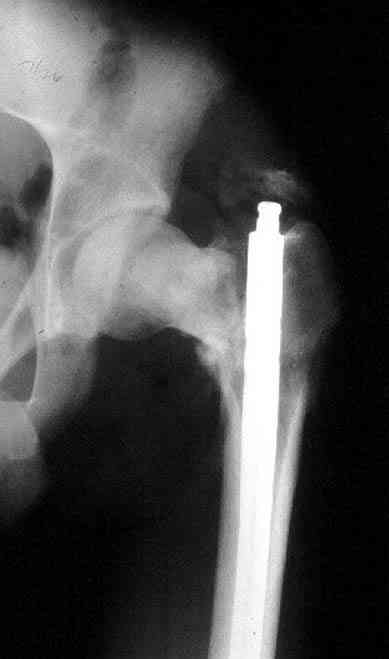

Установленный в бедро штифт, без стимуляции, не гарантирует сращение.

Учитывая молодой возраст больного, из всех рекомендуемых вариантов для лечения ложного сустава шейки предпочтительным является вальгусная остеотомия (на сайте имеются прежние разборы) из-за простоты исполнения и биомехнических преимуществ.

После удаления штифта нет необходимости проведения "стресса" на сращение, лучше провести фиксацию пластиной по два шурупа с каждой стороны.

Минимальный перкутанный доступ без ущерба сохранит сомнительное мозолеобразование и создаст условия для профилактики ложного сустава бедра.

Или при наличии ретроградной техники, короткий штифт с одним блокирующим шурупом дистально, создаст адекватную фиксацию и условия для быстрейшего восстановления.